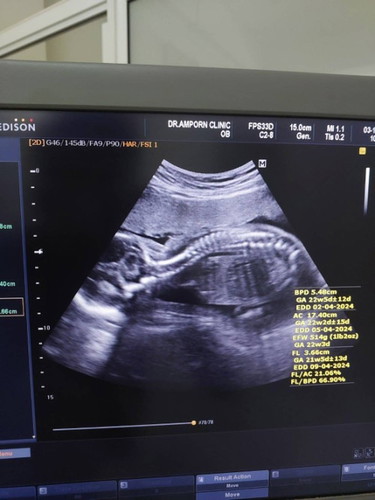

ลูกให้เห็นหน้าตอนกี่สัปดาห์คะ22Wแล้วคว่ำหน้าไม่ยอมให้เห็นเลยแล้วน้ำหนักเท่าไหร่กันบ้างคะอายุครรภ์22W 517 กรัมคุณหมอบอกลูกน้ำหนักน้อยไปค่ะ #ขอบคุณค่ะ

22weekเหมือนกันค่าาา คว่ำหน้าไม่ให้เห็นเหมือนกัน บ้านนี้น้ำหนัก457กรัม คุณหมอบอกตัวใหญ่นะคะ ไซส์ฝรั่งเลย😅😅😅

ลูกบ้านนี้เห็นหน้าตลอดเลยค่ะ เเต่อัลตราซาวด์ล่าสุด22W5d หั่นตูดให้เลยจ้า